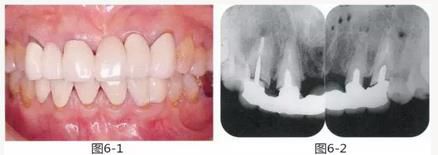

圖6-4,5

左上2,3和右上1,3存在齦下齲壞,但牙齒周圍有充足的角化齦。左上4和右上4頰側(cè)的角化齦較少。

圖6-6~8

左上3到右上3的牙齒,通過包含牙槽骨外科處理在內(nèi)的APF進行治療,確保了獲得biologic width所必需的、3mm以上的健全牙體組織。為獲得附著齦,使用FGG對左上4和右上4的牙齒進行了治療。

圖6-9 牙周外科治療5個月后,最終取模前的狀態(tài)?;乐車@得了充足的附著齦。